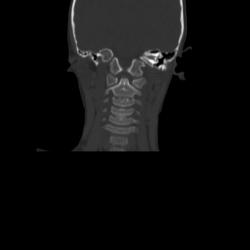

Ребенок 6 лет. Жалобы на выраженные боли в шейном отделе позвоночника. Со слов матери, боли в шее беспокоили длительное время. 2 недели отмечалась незначительная травма - девочка резко повернула голову в сторону, боли в шее услились. В настоящий момент  отмечаются выраженные боли в шее, резкое ограничение движений, повышение температуры тела, воспалительные изменения в анализах, (возможно, связанные с пиелонефритом, который также имеет место). Поступала с направительным диагнозом "ротационный подвывих атланта", однако данные рентгенографии заставили расширить круг диагностического поиска.Родовую травму мать отрицает. Хотелось бы узнать мнение уважаемых коллег.

Уважаемая коллега! С точки зрения классической рентгенологии (с учётом качества представленных снимков) могу высказать следующее:

- определяется выраженный антелистез тела С5;

- двуконтурность тел С3 и С5 может свидетельствовать о нарушении целостности костной ткани указанных тел позвонков;

- безусловно, межпозвонковые диски "поехали".

Вижу ещё раздвоенный axis.

Аксис не раздвоен, это нормальная картина для шести лет, просто верхушка зуба еще хрящевая.

Спасибо. Буду знать. По заданной теме: не хотелось бы быть освистанным, но смею предположить ювенильный ревматоидный артрит.

Случай помню. Закончилось все на удивление просто - после недели вытяжения петлей Глиссона боли ушли, движения в ШОП восстановились в полном объёме. Рентгенологические данные расценили как врожденную аномалию развития. Воспалительные изменения в анализах - как проявления пиелонефрита. В любом случае, из нашего поля зрения ребёнок ушел к нефрологам.